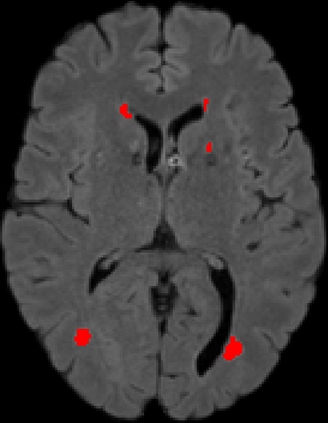

Assessment of lesions and their longitudinal progression from brain magnetic resonance (MR) images plays a crucial role in diagnosing and monitoring multiple sclerosis (MS). Machine learning models have demonstrated a great potential for automated MS lesion segmentation. Training such models typically requires large-scale high-quality datasets that are consistently annotated. However, MS imaging datasets are often small, segregated across multiple sites, with different formats (cross-sectional or longitudinal), and diverse annotation styles. This poses a significant challenge to train a unified MS lesion segmentation model. To tackle this challenge, we present SegHeD, a novel multi-dataset multi-task segmentation model that can incorporate heterogeneous data as input and perform all-lesion, new-lesion, as well as vanishing-lesion segmentation. Furthermore, we account for domain knowledge about MS lesions, incorporating longitudinal, spatial, and volumetric constraints into the segmentation model. SegHeD is assessed on five MS datasets and achieves a high performance in all, new, and vanishing-lesion segmentation, outperforming several state-of-the-art methods in this field.